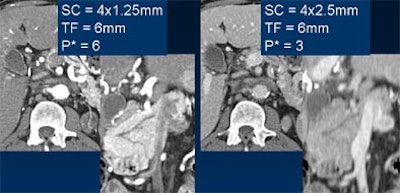

| Lower pitch (left) can be used to reduce artifacts in thin-section imaging, an approach that is particularly useful in the peripheral skeleton or in the C-spine, above. Images courtesy of Dr. Mathias Prokop. |

On the other hand, pitch can be lowered in order to decrease artifacts, he said. This technique is especially helpful in the peripheral skeleton, in the C-spine, or in any situation where patient dose is critical, and the radiologist wants to avoid the dose spike that comes with thinner collimation.